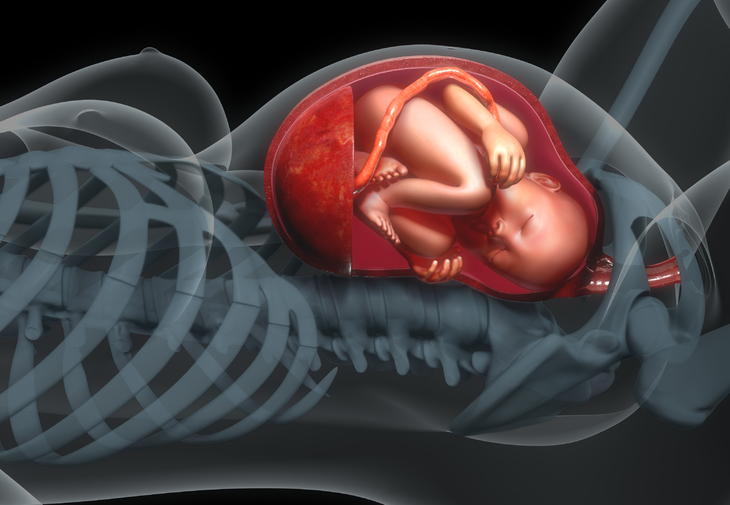

Stiai ca un bebelus invata inca din burtica sa-si suga degetul de la manuta? Si ca salta jucaus atunci cand o aude pe mami razand? Afla aici cateva lucruri interesante despre bebelusii din burtica.

Specialistii au aratat ca bebelusul inca din perioada intrauterina are tendinta de a folosi mai mult una dintre manute, iar preferinta se va pastra si dupa nastere.

Aproximativ in a 26-a saptamana de sarcina au fost vazuti la ecograf bebelusi care zambeau!

Fatul din burtica va incepe sa reactioneze la lumina inca incepand cu luna a 4-a, iar din aproximativ saptamana a 28-a va putea deschide ochii.

Au fost surprinse mai multe imagini in care bebelusul din burtica isi intorcea un pic capsorul sau isi acoperea fata cu manuta atunci cand spre burtica era indreptata o sursa mult prea puternica de lumina.

Inca de pe la 3 luni bebelusului din burtica i se dezvolta amprenta digitala.

Isi suge degetul

Obiceiul de a-si suge degetul mare de la manuta bebelusul il poate avea inca din burtica!